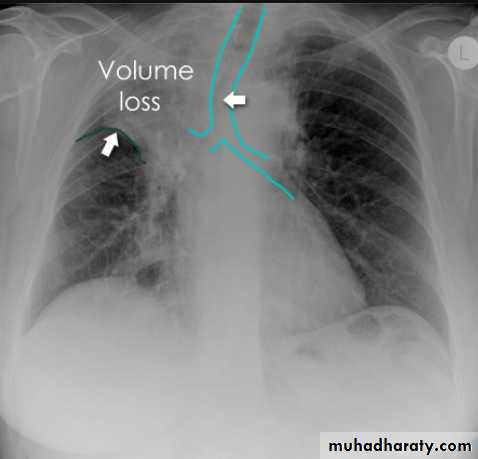

Left lower lobe collapse has distinctive features, and can be readily identified on frontal chest radiographs, provided attention is paid to the normal cardiomediastinal contours. The shadow cast by the heart does however make it harder to see than the right lower lobe collapse

Radiographic features

Left lower lobe collapse

is readily identified in a well penetrated film of a patient with normal sized heart, but can be challenging in the typical patient with collapse, namely unwell patients, with portable (AP) often under-penetrated films, often with concomitant cardiomegaly. Features to be observed include :

triangular opacity in the posteromedial aspect of the left lung

edge of collapsed lung may create a 'double cardiac contour'

left hilum will be depressed

loss of the normal left hemidaphgragmatic outline

loss of the outline of the descending aorta

Non-specific signs indicating left sided atelectasis are usually also be present including:

elevation of the hemidiaphragm

crowding of the left sided ribs

shift of the mediastinum to the left

On lateral projection the left hemidiaphragmatic outline is lost posteriorly and the lower thoracic vertebrae appear denser than normal (they are usually more radiolucent than the upper vertebrae) .